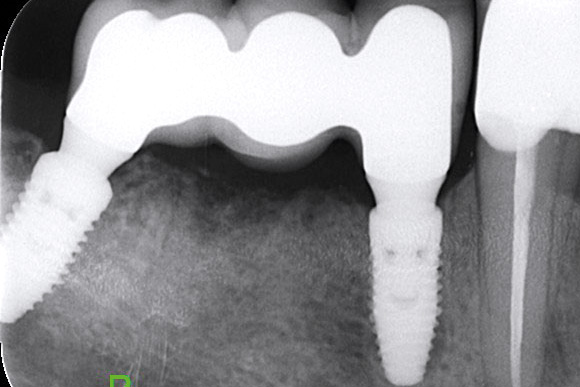

Multiple socket preservation in the mandibular with collacone® max – Dr. D. Jelušić